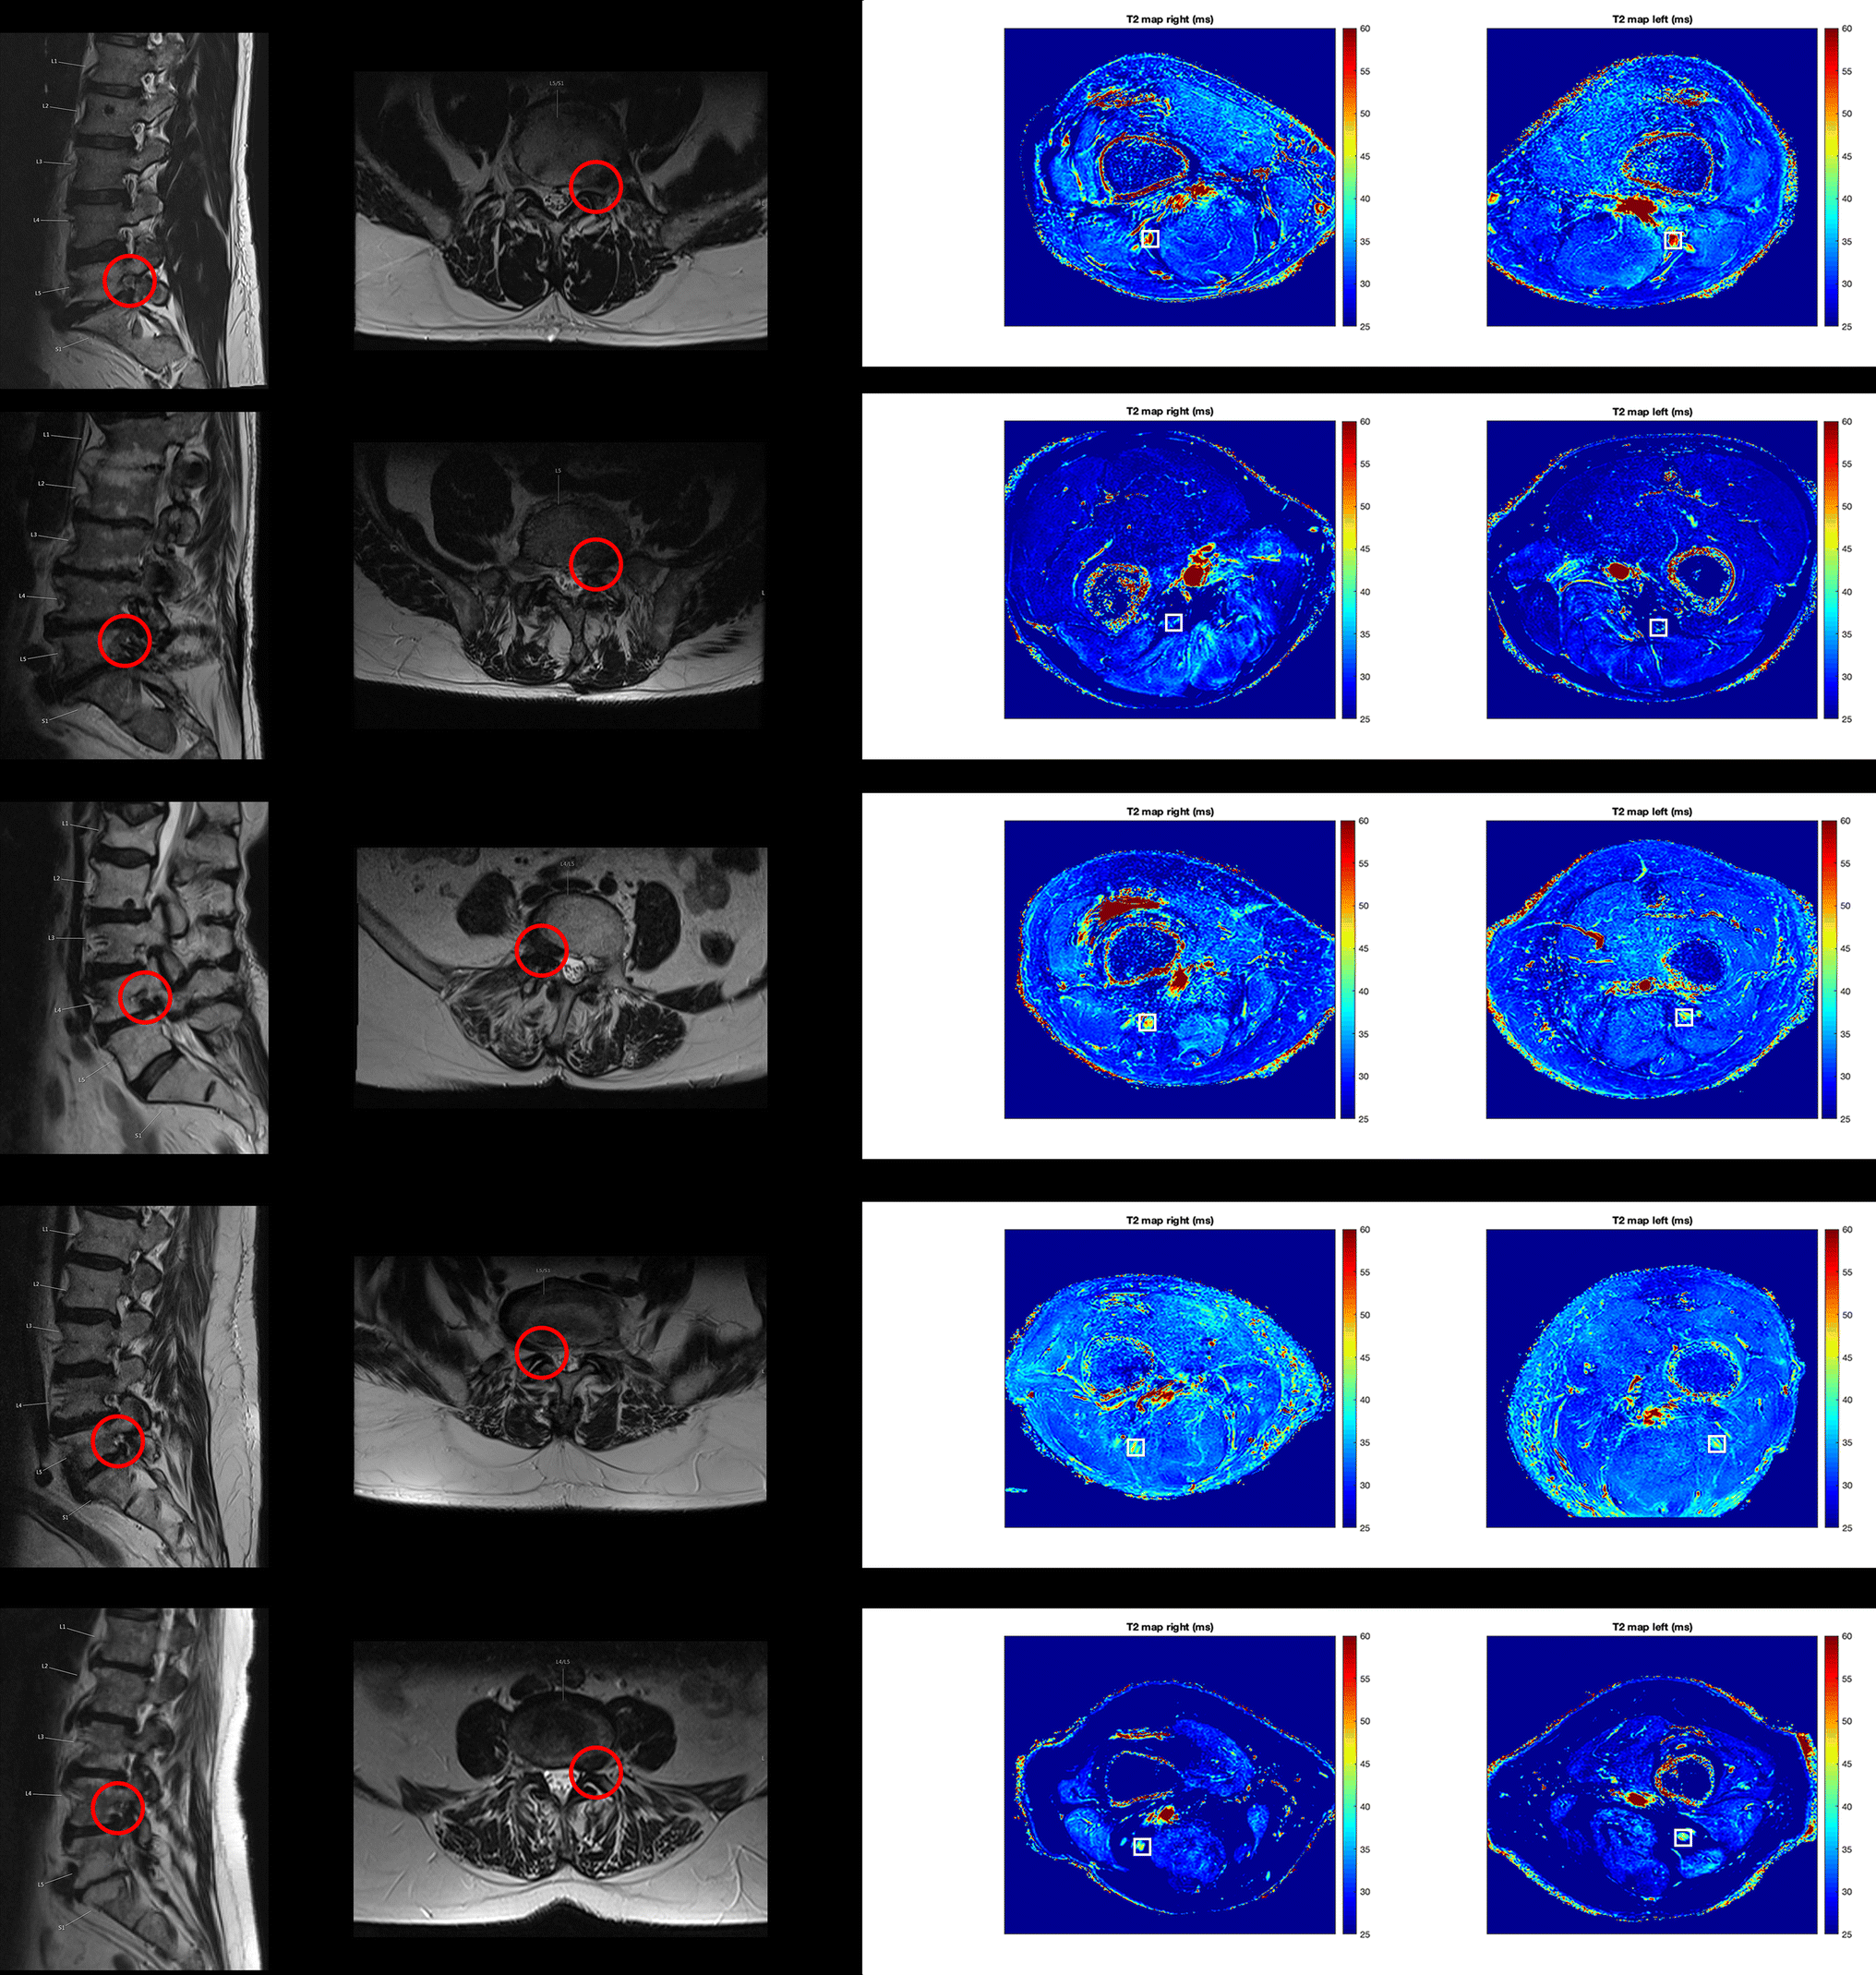

Figure 5 T2 Mapping Of The Distal Sciatic Nerve In Healthy Subjects And Patients Suffering From Lumbar Disc Herniation With Nerve Compression Springerlink